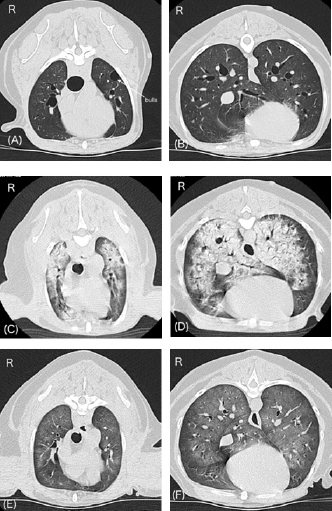

Approximately 15 minutes after being moved to the ward, the dog exhibited dyspnea and nose bleeding. The oral mucous membrane was pale, systolic blood pressure was >200 mmHg, and SpO2 ranged from 70% to 80%. The pulse rate was not recorded. A catecholamine crisis was suspected, and IV acepromazine (PromAce injectable; Boehringer Ingelheim Animal Health, Ridgefield, CT) at 0.01 mg/kg was administered for vasodilation and sedation. In addition, oxygen supply via a mask or flow-by was initiated after upper airway suctioning of blood and secretions. Following these treatments, the patient’s blood pressure decreased. Systolic and mean blood pressures were 140 and 100 mmHg, respectively. However, SpO2 remained at approximately 90% despite oxygen therapy, and respiratory distress was evident. Lung ultrasonography (LOGIQ e Premium; GE HealthCare, Tokyo, Japan) revealed a shred sign suggestive of lung consolidation with aeration in the left caudodorsal and perihilar lung regions. Multiple B lines suggestive of a wet lung were also observed in the left lung. The awake CT images taken 90 minutes after anesthetic recovery showed severe pulmonary consolidation with air bronchograms throughout all lung fields (Fig. 2C and D), and a decision was made to initiate ventilatory support under stable hemodynamics. Blood sampling for measurement of plasma catecholamine levels could not be performed given that our top priority was to stabilize a critical hypoxemia following the hypertensive crisis.

Fig. 2. Changes in lung CT images over time. A and B, images with breath hold at 10 cm H2O under general anesthesia before a hypertensive crisis. C and D, awake images 75 minutes after the onset of respiratory failure following a hypertensive crisis. E and F, images under spontaneous breathing 24 hours after onset of respiratory failure. Panels A, C, and E, cranial level; panels B, D, and F, caudal level. A and B show normal canine lungs except for the presence of bulla. C and D reveal acute onset of severe pulmonary consolidation with air bronchograms throughout all lung fields compared with A and B. E and F reveal dramatic improvement of pulmonary consolidation compared with C and D. The patient was connected to an intensive care ventilator (SERVO-air; Fukuda Denshi, Tokyo, Japan), and isoflurane anesthesia was discontinued. General anesthesia was maintained with propofol (Propofol 1% IV injectable; Pfizer Japan Inc., Tokyo, Japan) and fentanyl (Terumo Corporation, Tokyo, Japan) with constant-rate infusion (0.3 mg/kg/minute and 0.1 μg/kg/minute, respectively). An additional IV bolus of propofol, fentanyl, or midazolam (Maruishi Pharmaceutical. Co., Ltd., Osaka, Japan) was administered to maintain the patient’s ventilatory synchrony. Pressure-support ventilation with continuous positive airway pressure (CPAP) was initiated and maintained overnight. The initial ventilatory settings were: support pressure, 8 cm H2O (ΔPsupport); CPAP, 5 cm H2O; time for pressure to rise to the target pressure, 0.15 seconds; expiration trigger sensitivity, 30%; and flow trigger, 1.0 l/minute. During ventilation, ΔPsupport ranged from 7 to 10 cm H2O, and the tidal volumes were between 8 and 14 ml/kg. The fraction of inspired oxygen (FiO2) had gradually decreased to 30% by the next morning, while SpO2 was maintained above 95%. In addition to ventilatory management, 0.01 mg/kg of IV acepromazine was administered every 4 hours for additional sedation and prophylaxis of hypertension. Fluid therapy, consisting of a hypotonic crystalloid solution (Soldem3; Terumo Corporation, Tokyo, Japan) at a rate of 1 ml/kg/hour was maintained. The total volume, including other drugs was calculated as 2–3 ml/kg/hour. Three bolus doses of IV furosemide (0.5 or 1 mg/kg) were used to maintain a negative fluid balance. Cefazoline (LTL Pharma Co., Ltd., Tokyo, Japan; 20 mg/kg IV) was administered every 8 hours as a prophylactic antibiotic. During ventilation, the patient’s hemodynamics remained stable, and the spontaneous RR gradually decreased to 20–30 breaths/minute. On the morning after 14 hours of ICU ventilation, PaO2 and PaCO2 were 93 and 33 mmHg, respectively. The P/F ratio was calculated to be 310. The ventilatory settings were: ΔPsupport, 7 cm H2O; CPAP, 5 cm H2O; and FiO2, 0.3. No cardiorespiratory instability was observed. In addition, only a few B lines were observed on lung ultrasonography. Improvement in the pulmonary CT images was also noted (Fig. 2E and F). Therefore, an attempt to wean the patient from the ventilator was initiated 15 hours after starting ICU ventilation (24 hours after the onset of respiratory failure). To allow weaning from the ventilator, constant-rate infusions were discontinued. Ten minutes later, the patient was no longer accepting the endotracheal tube, at which time the patient was extubated. Blood sputum adhesion was observed at the tip of the extubated tube. The patient was able to breathe effectively with some respiratory effort, and SpO2 was 96% under nasal oxygen supply at 0.5 l/minute. PaO2 and PaCO2 were 77 and 27 mmHg, respectively. The body weight after weaning was 170 g less than that before the onset of respiratory failure. Cefazoline and enrofloxacin (Baytril 2.5% injection for dogs and cats; Elanco Japan, Tokyo, Japan) were administered as prophylactic antibiotics during hospitalization. In addition, oral treatment with pimobendane (VETMEDIN chewable tablet; Boehringer Ingelheim Animal Health, Tokyo, Japan) was resumed. Oxygen therapy was continued for 24 hours after extubation. Finally, the dog was discharged 3 days after weaning from ventilation. The owner refused additional treatment for the intra-abdominal lesions. The dog survived without any respiratory or neurological complications for 14 months after weaning from mechanical ventilation. DiscussionTo the best of our knowledge, this is the first clinical case report describing the successful recovery and discharge of a dog with acute respiratory failure following hypertensive crisis. There is a high possibility that this hypertensive crisis was associated with a catecholamine storm due to a preexisting pheochromocytoma or paraganglioma. In pheochromocytoma, a perianesthetic catecholamine storm may be induced by many factors, including stress, changes in intra-abdominal pressure, hypoventilation, drugs causing histamine release (e.g., morphine and meperidine), and drugs affecting the sympathetic nervous system (e.g., ketamine, ephedrine, and metoclopramide) (Fischer, 2022). In the present dog, overweight and cystic disease of the left kidney may have aggravated the changes in intra-abdominal pressure occurring during positional changes. There are pros and cons (Bessell-Browne and O’Malley, 2007), IV administration of iodine contrast agents may also induce catecholamine storm in patients with pheochromocytoma. The triggers of the hypertensive crisis in the present dog may have been stress, changes in intra-abdominal pressure, or the iodine-based contrast agent administered for the contrast-enhanced CT scan. Hypertensive crisis is a major complication of pheochromocytoma and paraganglioma (Galac and Korpershoek, 2017; Ng et al., 2023). In humans, acute pulmonary edema is a manifestation of hypertensive crisis in pheochromocytoma and can be either cardiogenic or noncardiogenic (Galac and Korpershoek, 2017; Ng et al., 2023). Cardiogenic pulmonary edema is more common and may be due to catecholamine-induced type of cardiomyopathy, including dilated cardiomyopathy, hypertrophic cardiomyopathy, or Takotubo cardiomyopathy in humans (Kumar et al., 2021; Ng et al., 2023). However, cardiovascular abnormalities were not detected in the present case, except for mild-to-moderate MMVD, and no evidence of elevated left atrial pressure leading to cardiogenic pulmonary edema was obtained on preanesthetic examination. During mechanical ventilation, no findings suggestive of these cardiomyopathies were observed by subjective echocardiography, and the hemodynamics remained stable without cardiovascular medication. On the other hand, noncardiogenic pulmonary edema is rare in humans (Ng et al., 2023). The cause of noncardiogenic pulmonary edema in cases of pheochromocytomas is similar to that of neurogenic pulmonary edema. The pathogenesis of neurogenic pulmonary edema is also associated with catecholamine storms (Davison et al., 2012; Drobatz, 2019; Unger and Martin, 2023). In this pathology, high catecholamine concentration can cause a sudden increase in pulmonary capillary pressure due to massive vasoconstriction and alter pulmonary capillary permeability (Davison et al., 2012; Drobatz, 2019; Unger and Martin, 2023). Unfortunately, we did not measure plasma catecholamine levels during the hypertensive crisis and, therefore, lack direct proof of a catecholamine storm in the present case. The observation of a high urinary-free normetanephrine to creatinine ratio on the initial examination day suggests that catecholamine storms were occurring randomly in this patient. The common radiographic findings of neurogenic pulmonary edema in dogs are bilateral, symmetric, multifocal, mixed alveolar to interstitial lung patterns, focused on the caudal lung lobe or distributed throughout all lung fields (Bouyssou et al., 2017). The CT and lung ultrasonography images of the present dog were consistent with previous reports. We surmise that the main pathogenesis of acute respiratory failure in the present dog was a noncardiogenic pulmonary edema, such as a neurogenic pulmonary edema induced by a catecholamine storm. The involvement of MMVD may have exacerbated the pulmonary edema. A productive cough associated with pink, frothy nasal discharge or sputum, commonly seen in severe cardiogenic pulmonary edema (Oyama, 2019), was not observed in the present dog. In addition, endotracheal tube suctioning during mechanical ventilation was not required. A small amount of blood sputum was observed at the tip of the extubated tube, but this may have originated from aspiration of nasal bleeding following hypertensive crisis. Initially, it was also suspected that the acute dyspnea was caused by upper airway obstruction following nasal bleeding consequent to the hypertensive crisis. However, despite prompt efforts to secure the upper airway through sedation, suction, and mouth opening, we observed no improvement in respiratory status, and no obstruction of the airway was observed at the time of CT imaging. In the present case, the onset and progression of pulmonary edema were extremely rapid. Severe oxygenation failure was detected based on the P/F ratio before initiation of ICU ventilation. Pulmonary edema in the present dog was treated with mechanical ventilation and negative fluid balance (minus 170 g based on body weight measurements) after the administration of furosemide. In this dog, pressure-support ventilation with CPAP was adopted to reduce spontaneous respiratory effort and improve oxygenation. The response to treatment was good, and the improvement in pulmonary edema was dynamic. The dog was extubated after mechanical ventilation for 24 hours. Similar to the present case, rapid onset and recovery of neurogenic pulmonary edema have been reported in dogs (Drobatz et al., 1995; Drobatz, 2019; Herrería-Bustillo et al., 2022; Nemi et al., 2023; Unger and Martin, 2023). A high mortality rate was observed in dogs treated with mechanical ventilation for neurogenic pulmonary edema (Drobatz et al., 1995; Nemi et al., 2023). The unfavorable outcomes are attributed to the severity of the underlying disease rather than to the complications of pulmonary edema or mechanical ventilation (Drobatz et al., 1995; Drobatz, 2019; Unger and Martin, 2023). In the present case, no additional hypertensive crisis was observed during mechanical ventilation. To control hypertensive crisis in pheochromocytoma, short-acting injectable alpha-blockers, such as phentolamine, are commonly administered. On the other hand, long-acting oral alpha-blockers, such as phenoxybenzamine, are commonly used for preoperative stabilization in pheochromocytoma (Herrera et al., 2008). Acepromazine is a long-acting injectable major tranquilizer with simultaneous alpha 1 blockade. The main reason for using acepromazine during ICU ventilation was our expectation of obtaining hemodynamic stabilization in the present dog, similar to preoperative alpha-blocker therapy in pheochromocytoma. Simultaneously, acepromazine likely contributed to sedation during mechanical ventilation. We believe that hemodynamic stability was key to the successful treatment of this dog. This case illustrates the successful weaning and hospital discharge of a dog with acute respiratory failure following a hypertensive crisis requiring mechanical ventilatory management for 24 hours. A catecholamine storm associated with presumed pheochromocytoma or paraganglioma may have caused pulmonary edema in the present dog. The onset and progression of the pulmonary edema were extremely rapid. However, improvement in pulmonary edema was also rapid. In addition to prompt diagnosis and aggressive therapeutic intervention with mechanical ventilation, the achievement of hemodynamic stability may have contributed to a good prognosis; in this case of pulmonary edema following a hypertensive crisis in a dog, we attribute to a catecholamine storm induced by a presumed pheochromocytoma or paraganglioma. AcknowledgmentsNot applicable. Conflict of interestThe authors declare that there is no conflict of interest. FundingNo sources of funding for the work presented here. Author contributionsJT and NO performed anesthesia and ventilatory management of this patient. JT wrote the manuscript. Internal medicine veterinarians NN and SY performed the case evaluation and follow-up. GS was responsible for diagnostic imaging. All authors discussed this patient and approved this manuscript. Data availabilityAll data supporting the findings of this case report are available within the manuscript. ReferencesBessell-Browne, R. and O’Malley, M.E. 2007. CT of pheochromocytoma and paraganglioma: risk of adverse events with i.v. administration of nonionic contrast material. AJR. Am. J. Roentgenol. 188, 970–974. Bouyssou, S., Specchi, S., Desquilbet, L. and Pey, P. 2017. Radiographic appearance of presumed noncardiogenic pulmonary edema and correlation with the underlying cause in dogs and cats. Vet. Radiol. Ultrasound. 58, 259–265. Cagle, L.A., Hopper, K. and Epstein, S.E. 2022. Complications associated with long-term positive-pressure ventilation in dogs and cats: 67 cases. J. Vet. Emerg. Crit. Care. (San Antonio). 32, 376–385. Davison, D.L., Terek, M. and Chawla, L.S. 2012. Neurogenic pulmonary edema. Crit. Care. 16, 212. Drobatz, K.J. 2019. Neurogenic pulmonary edema. In Textbook of small animal emergency medicine, 1st ed. Eds., Drobatz, K.J., Hopper, K., Rozanski, E. and Silverstein, D.C. Hoboken, NJ: Willey Blackwell, pp: 247–252. Drobatz, K.J., Saunders, H.M., Pugh, C.R. and Hendricks, J.C. 1995. Noncardiogenic pulmonary edema in dogs and cats: 26 cases (1987-1993). J. Am. Vet. Med. Assoc. 206, 1732–1736. Edwards, T.H., Erickson Coleman, A.E., Brainard, B.M., DeFrancesco, T.C., Hansen, B.D., Keene, B.W. and Koenig, A. 2014. Outcome of positive-pressure ventilation in dogs and cats with congestive heart failure: 16 cases (1992-2012). J. Vet. Emerg. Crit. Care. (San Antonio). 24, 586–593. Fischer, B.L. 2022. Endocrine disease. In Canine and feline anesthetic and co-existing disease, 2nd ed. Eds., Johnson, R.A., Snyder, L.B.C. and Schroeder, C.A. Hoboken, NJ: Willey Blackwell, pp: 299–335. Galac, S. and Korpershoek, E. 2017. Pheochromocytomas and paragangliomas in humans and dogs. Vet. Comp. Oncol. 15, 1158–1170. Gombert, A., Diana, A., Hecht, S., Nicoli, S., Fracassi, F., Mortier, J., Reyes-Gomez, E. and Pey, P. 2022. Imaging features of retroperitoneal extra-adrenal paragangliomas in 10 dogs. Vet. Radiol. Ultrasound. 63, 393–402. Herrera, M.A., Mehl, M.L., Kass, P.H., Pascoe, P.J., Feldman, E.C. and Nelson, R.W. 2008. Predictive factors and the effect of phenoxybenzamine on outcome in dogs undergoing adrenalectomy for pheochromocytoma. J. Vet. Intern. Med. 22, 1333–1339. Herrería-Bustillo, V.J., Adamantos, S., Lamb, C.R., García-Arce, M., Thomas, E., Saiz-Álvarez, M.R., Cook, S. and Cortellini, S. 2022. Retrospective evaluation of negative-pressure pulmonary edema in dogs (2006-2018): 35 cases. J. Vet. Emerg. Crit. Care. (San Antonio). 32, 397–404. Hopper, K., Haskins, S.C., Kass, P.H., Rezende, M.L. and Aldrich, J. 2007. Indications, management, and outcome of long-term positive-pressure ventilation in dogs and cats: 148 cases (1990-2001). J. Am. Vet. Med. Assoc. 230, 64–75. Kumar, A., Pappachan, J.M. and Fernandez, C.J. 2021. Catecholamine-induced cardiomyopathy: an endocrinologist’s perspective. Rev. Cardiovasc. Med. 22, 1215–1228. Nemi, J.R., Hopper, K. and Epstein, S.E. 2023. Retrospective evaluation of noncardiogenic pulmonary edema in dogs and cats (2000-2021): 31 cases. J. Vet. Emerg. Crit. Care. (San Antonio). 33, 354–359. Ng, D.Z., Than Yu, K.P. and Rajkanna, J. 2023. Acute pulmonary edema as a cardiovascular manifestation of pheochromocytoma. Cureus 15, e33675. Oyama, M.A. 2019. Cardiogenic pulmonary edema. In Textbook of small animal emergency medicine, 1st ed. Eds., Drobatz, K.J., Hopper, K., Rozanski, E. and Silverstein, D.C. Hoboken, NJ: Willey Blackwell, pp: 242–246. Sasaki, N., Ikenaka, Y., Inoue, Y., Ichise, T., Nagata, N., Ishizuka, M., Nakayama, S.M., Nakamura, K. and Takiguchi, M. 2021. Urinary free metanephrines measurement in dogs with adrenal gland diseases using a new simple liquid chromatography tandem mass spectrometry method. J. Vet. Med. Sci. 83, 648–655. Summers, C., Todd, R.S., Vercruysse, G.A. and Moore, F.A. 2022. Acute respiratory failure. Perioper. Med. 2022, 576–586. Unger, K. and Martin, L.G. 2023. Noncardiogenic pulmonary edema in small animals. J. Vet. Emerg. Crit. Care. (San Antonio). 33, 156–172. | ||